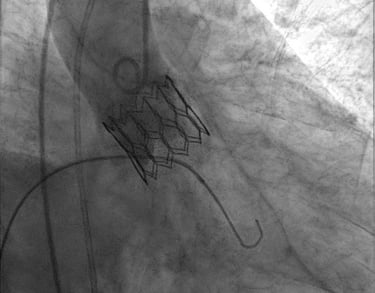

Impianto transcatetere di valvola aortica (TAVI)

Procedura riservata a pazienti che sono affetti da stenosi valvolare aortica severa ma che e’ preferibile non trattare con la chirurgia tradizionale.